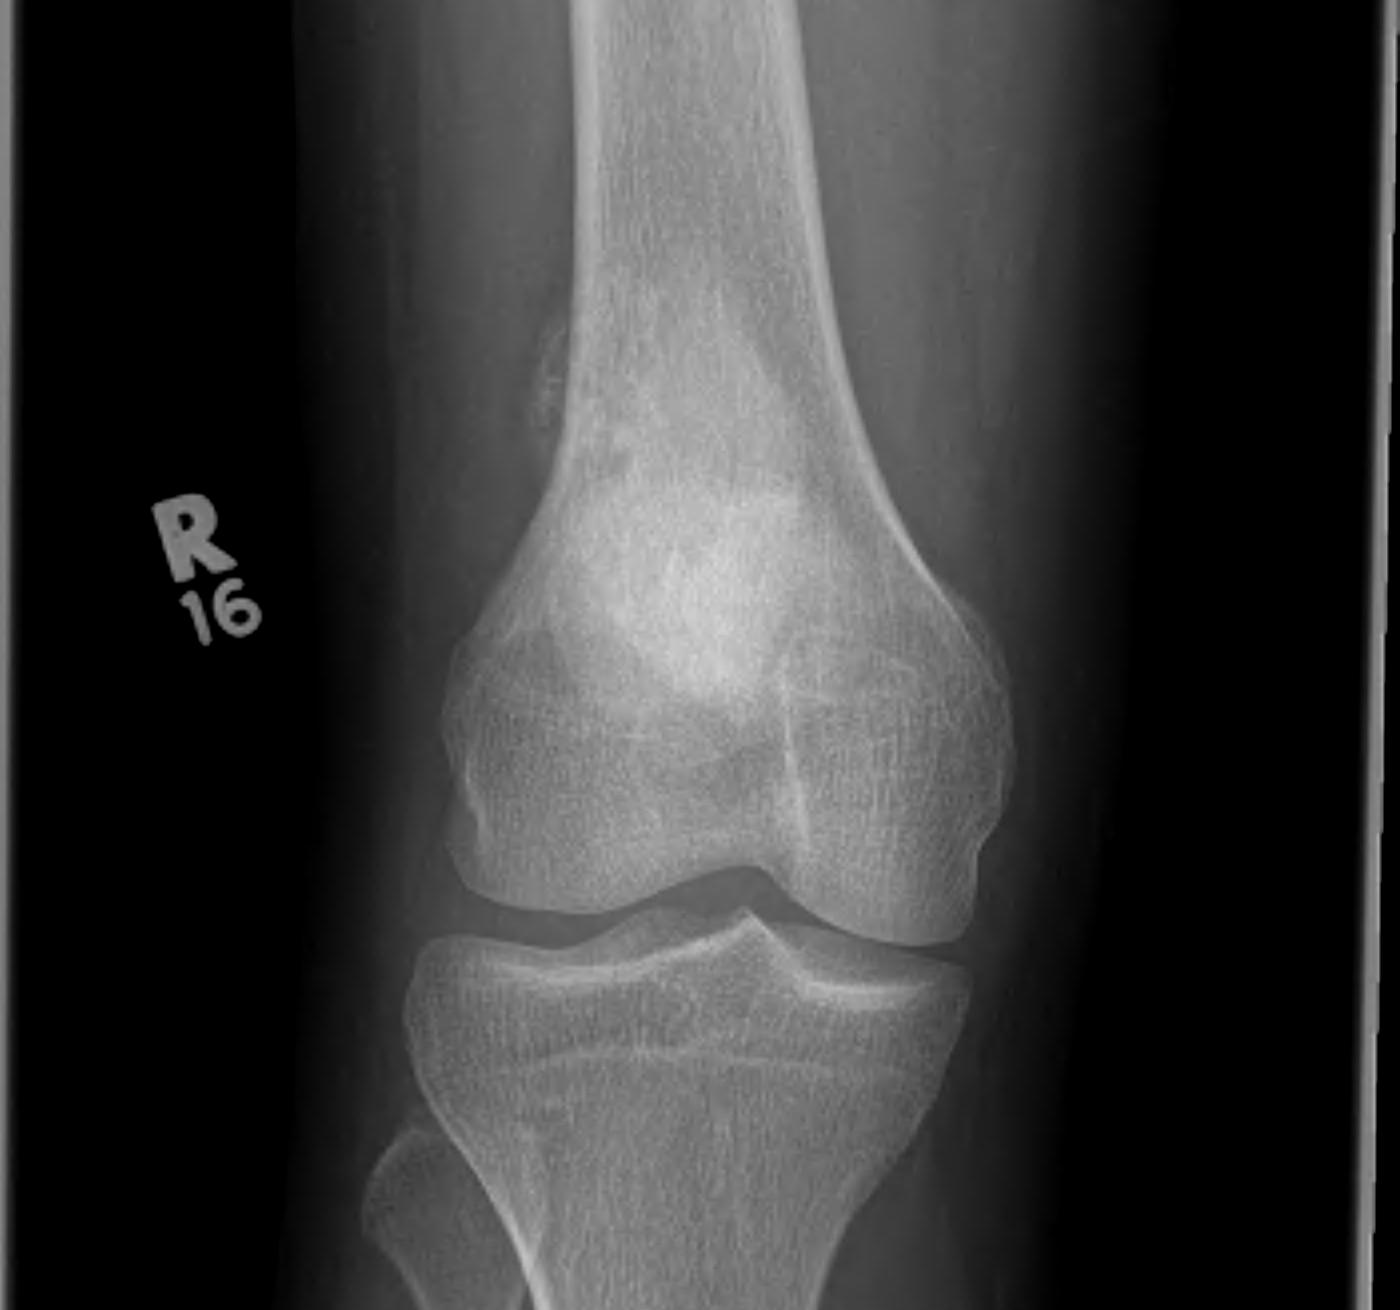

X-ray

May look like osteochondroma

- large lobulated broad-based lesion

- mature bone arising from cortex

- underlying cortex may be thickened

- 25% invade periosteum

"String Sign"

- wraps around bone with intervening periosteum

- well-defined radiolucent line between lesion & cortex

Parosteal osteosarcoma distal femur

Parosteal Osteosarcoma proximal tibia